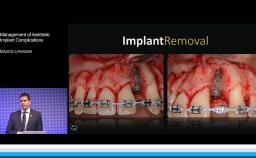

The lecture presents concepts for the treatment of patients with implant complications. The first part concentrates on esthetic failures related to surgical procedures. Several patient cases are shown to illustrate both surgical and prosthetic concepts for the management of complications. In particular, this presentation demonstrates the reverse-torque removal of incorrectly placed implants as well as subsequent bone augmentation. The second part of the lecture focuses on how these types of problems can be avoided from the outset by proper diagnosis, treatment planning, and treatment execution. The lecturer presents the benefits of the ITI and the Online Academy in educating young clinicians about crucial factors that affect each of these phases. Those factors include timing of the implant placement, socket management, and esthetic risk assessment. Finally, long-term data on patients with fixed implant-supported prostheses from the University of Bern is presented.